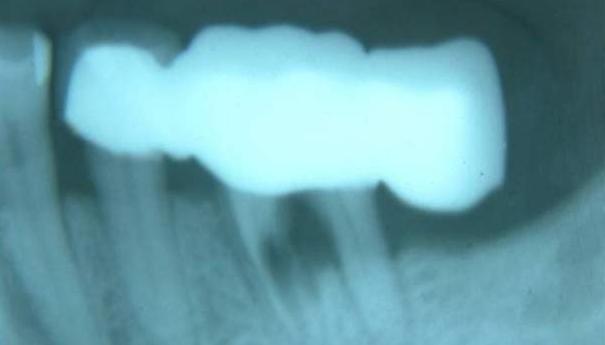

定义:固定牙桥是这十几年来,被使用频率比较高的一种牙体修复技术,是固位体、桥体、连接体组合义齿;

通常是利用缺牙旁边一端或两端的健康牙齿作为基牙,将固定体粘合在基牙上,在通过用连接体与义齿连接,呈现一种具有咬合力的整体结构。

优势:安装成功后可以恢复60%的咀嚼功能,且相较于活动假牙等修复方法,固定牙桥使用时间更长,在正常情况下使用寿命可以达到十年左右,且价格便宜,单颗价格不到种植牙的三分之一。

劣势:除马里兰桥之外,传统牙桥和单端牙桥在基牙准备时都会对缺牙旁边牙齿造成磨损,磨损既不可逆,为了一颗坏牙会损坏两颗邻牙,且由于牙桥的结构比较复杂,如果不非常注意清洁,会有龋齿的隐患。